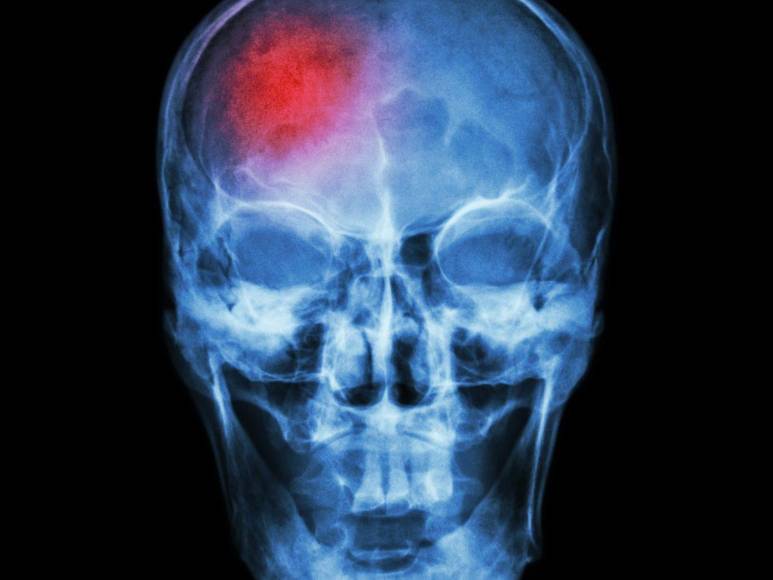

El exdiputado del Partido Nacional, Oswaldo Ramos Soto, quien fue hospitalizado de emergencia la noche del martes -6 de agosto- actualmente se encuentra en la unidad de Cuidados Intensivos debido a una complicación cerebrovascular, según anunció su familia, pero ¿Qué es una enfermedad cerebrovascular? ¿Cuáles son sus causas, síntomas y tratamiento? Te lo decimos en la siguiente galería.

Una afección cerebrovascular es aquella en la que el flujo sanguíneo hacia el cerebro se ve comprometido en el paciente y puede desencadenarse lentamente o de manera súbita, provocando la necesidad urgente de la intervención médica, de acuerdo a especialistas de Mayo Clinic y MedlinePlus del departamento de Salud estadounidense.

Dentro de esta afección existen dos tipos de complicaciones como ser: el accidente cerebrovascular isquémico que se produce cuando el flujo sanguíneo hacia una parte del cerebro se obstruye o reduce, impidiendo que el tejido cerebral reciba oxígeno y nutrientes necesarios. Las neuronas comienzan a morir en minutos. Además, el accidente cerebrovascular hemorrágico que ocurre cuando un vaso sanguíneo en el cerebro se rompe, causando sangrado. La sangre acumulada aumenta la presión en el cerebro y daña las neuronas. En el caso particular del político hondureño no ha sido revelado la gravedad de su situación.